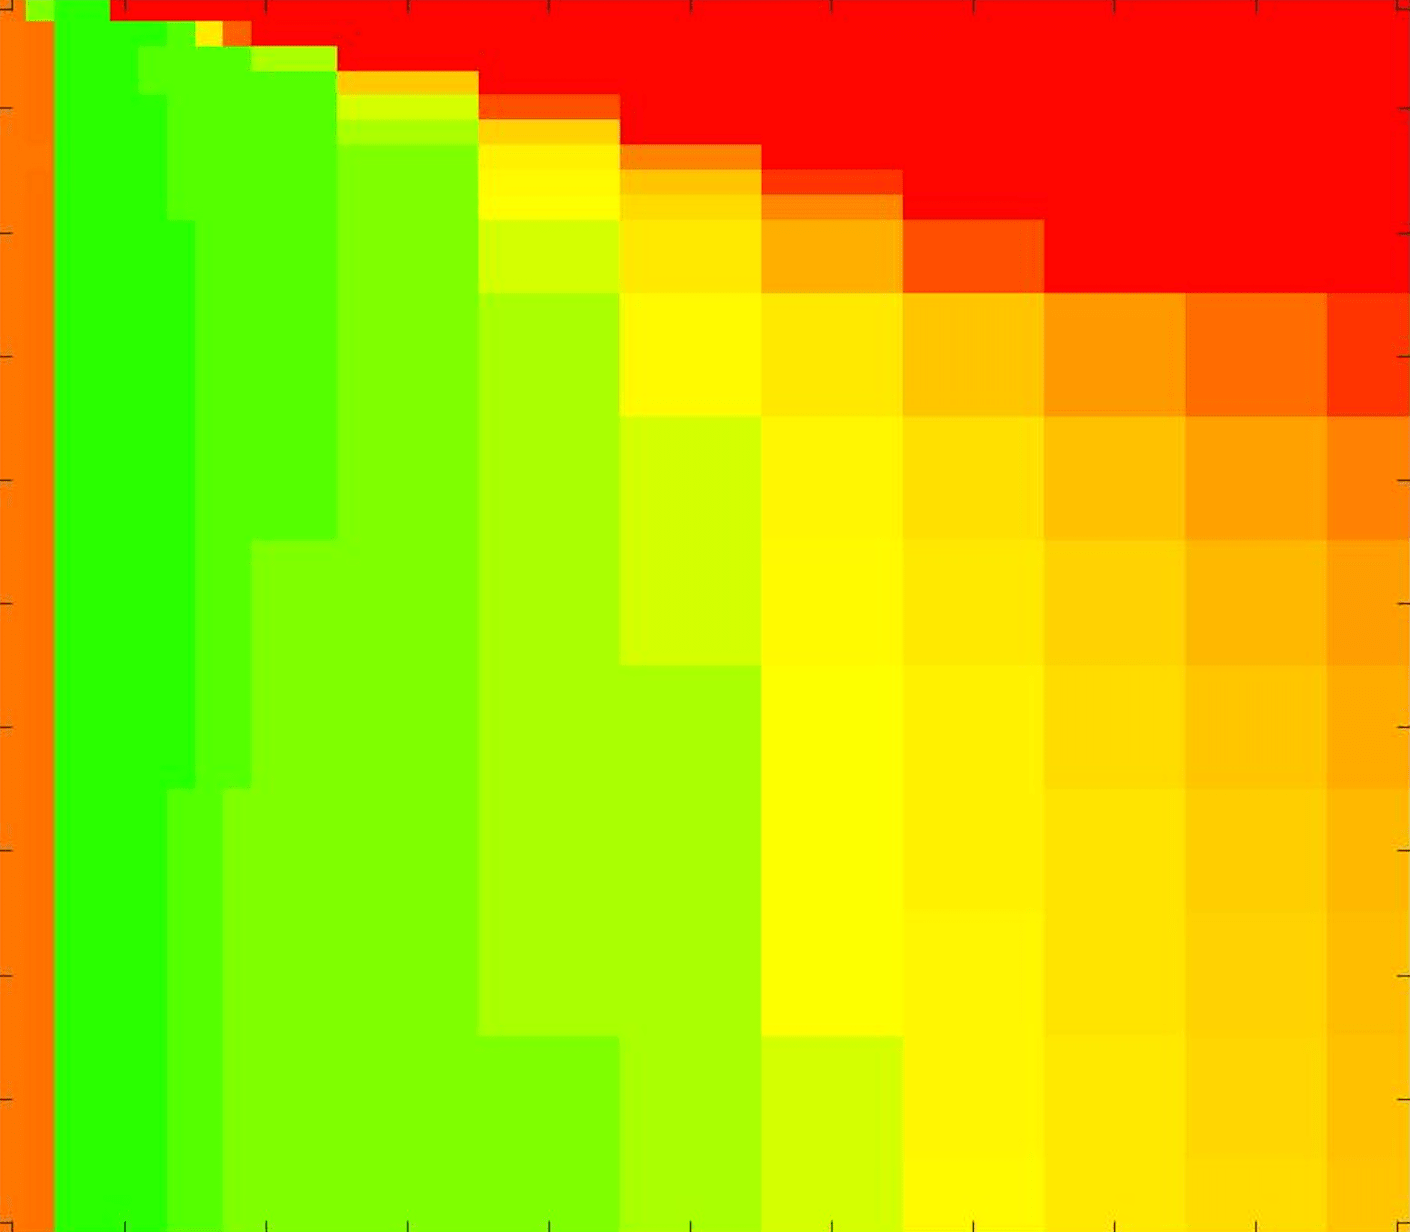

where refers to the number of points in the enclosed region. This takes values in the range , with higher TC values indicating a more accurate segmentation. In the following we will represent accuracy visually from red () to green (), with the intermediate scaling of colours used shown in Fig. 8. This will be particularly relevant in §7.2.

The TC values for the parameter sets are presented as heatmaps in Figs. 11–13. A heatmap is a convenient way to display accuracy results for hundreds of tests concisely. In Fig. 9 we give an example heatmap with the same axes used for those in Figs. 11–13. For each of the combinations of parameter values we give the TC value of the segmentation result and represent it by the appropriate colour. The corresponding colour scale is shown in Fig. 8. Qualitatively, the more green areas of the heatmap the more accurate the model is for a wider set of parameters. Example results for Test Image 5 when varying (with ) for the proposed model are given in Fig. 10. Here it can be seen what each accuracy result corresponds to visually.

Note. The axes have been removed from the heatmaps in Figs. 11–13 for presentational clarity. However, to be explicit, the axes used in all heatmaps are the same as those in Fig. 9.

Synthetic Images. These results are presented in Fig. 11. For Test Images 1–2 we see poor parameter robustness from all competing models, except for GAV which performs reasonably well. However, the proposed model has minimal parameter sensitivity for these images, with good results achieved for almost every combination of values tested. For Test Image 3 all models have a reasonable parameter range (except for RSF), however the proposed model gives better quality results for a wider parameter range. The other models achieve reasonable results here as the foreground intensity of the ground truth is greater than the background , whereas for Test Images 1–2 they are equal . These results highlight the key advantage of the proposed model.

Real Images. In Fig 12 we present results for Test Images 4–6. Here, the proposed model performs in a similar way to its competitors because these images are more typical selective segmentation problems in the sense that there is a clear distinction between the foreground and background intensities. In particular, the values in each case are: Test Image 4 , Test Image 5 , and Test Image 6 . It can be seen that the proposed model is competitive compared to previous approaches. The performance is quite poor for Test Image 5, but is arguably still the best for this challenging case. In Fig. 13 we present results for Test Images 7–9. Here the proposed model outperforms previous approaches significantly for each image. This is mainly due to the type of image considered. Specifically, the true intensities are: Test Image 7 , Test Image 8 , and Test Image 9 . The proposed model is capable of achieving results where , with other models failing completely in these cases.